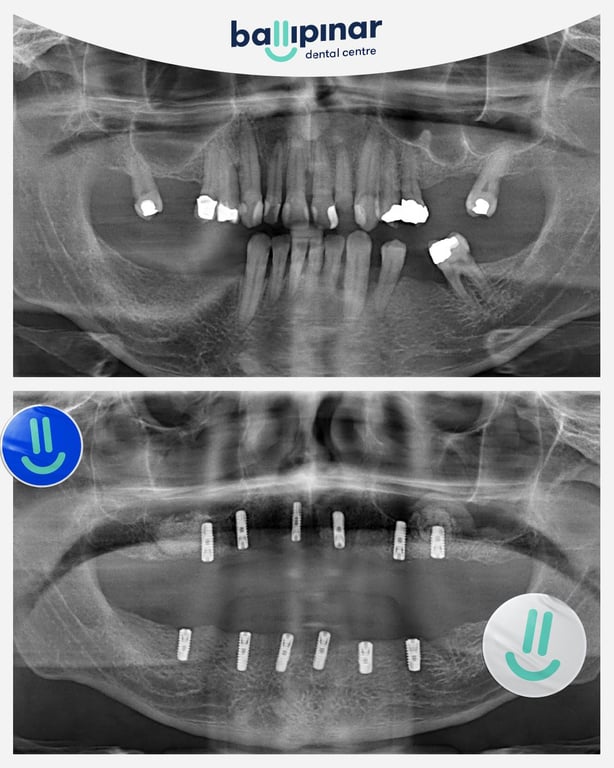

Dental implants Before & After

Explore all the before and after photos of dental implant procedures performed by Ballipinar in Turkey. Contact us today to achieve a beautiful smile.